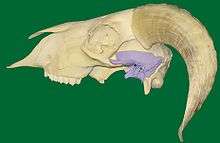

The temporomandibular joint is the joint of the jaw, sometimes referred to as the TMJ. It is a bilateral synovial articulation between the upper temporal bone and the lower mandible; it is from these bones that its name is derived.

The main components are the joint capsule, articular disc, mandibular condyles, articular surface of the temporal bone, temporomandibular ligament, stylomandibular ligament, sphenomandibular ligament, and lateral pterygoid muscle.

The lower joint compartment formed by the mandible and the articular disc is involved in rotational movement—this is the initial movement of the jaw when the mouth opens. The upper joint compartment formed by the articular disc and the temporal bone is involved in translational movement—this is the secondary gliding motion of the jaw as it is opened widely. The part of the mandible which mates to the under-surface of the disc is the condyle and the part of the temporal bone which mates to the upper surface of the disk is the articular fossa or glenoid fossa or mandibular fossa.

Each temporomandibular joint is classed as a "ginglymoarthrodial" joint since it is both a ginglymus (hinging joint) and an arthrodial (sliding) joint.[7] The condyle of the mandible articulates with the temporal bone in the mandibular fossa. The mandibular fossa is a concave depression in the squamous portion of the temporal bone.